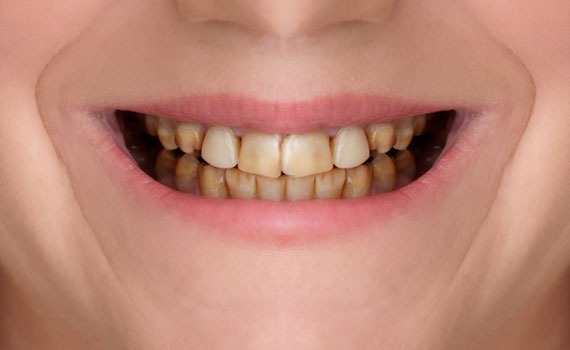

Diş Beyazlatma

Dişlerin yapısal olarak kendine has bir rengi vardır. Yenilen yemekler, sigara, çay, kahve, kola, şarap, vişne vs gibi etmenler dişlerde...

Bleaching